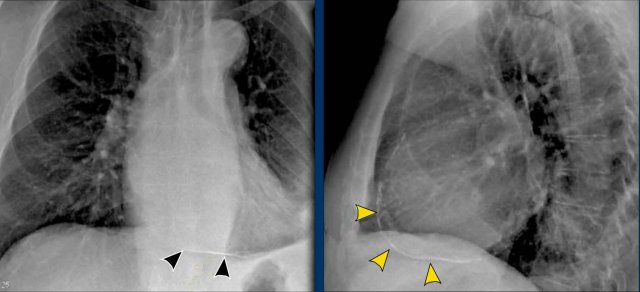

Displacement of the Azygoesophageal Line (1) – Hiatal hernia

A hiatal hernia (arrowheads) is the most common cause of displacement of the azygoesophageal line as seen on the PA-view.

Notice the air within the hernia on the lateral view (black arrow).

• Case Example

A patient with bilateral carcinomatous pleuritis.

Findings

• Complete opacification of the right hemithorax.

• Air bronchogram in the right main bronchi (arrowheads), indicating compression atelectasis of the lung due to massive effusion.